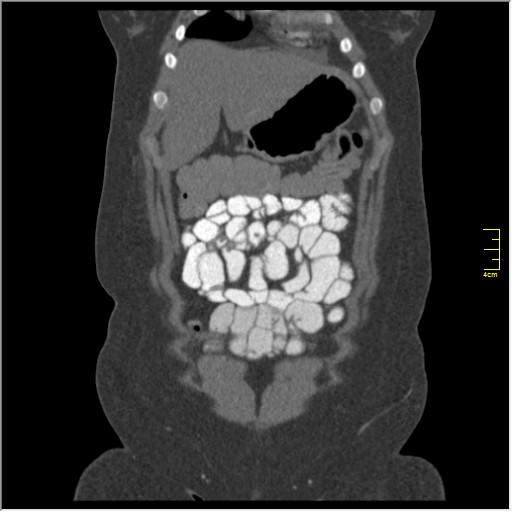

КТ энтерография

Демонстрационные изображение, оцените возможности метода! Толщина среза реконструкции 0.5-1 мм.